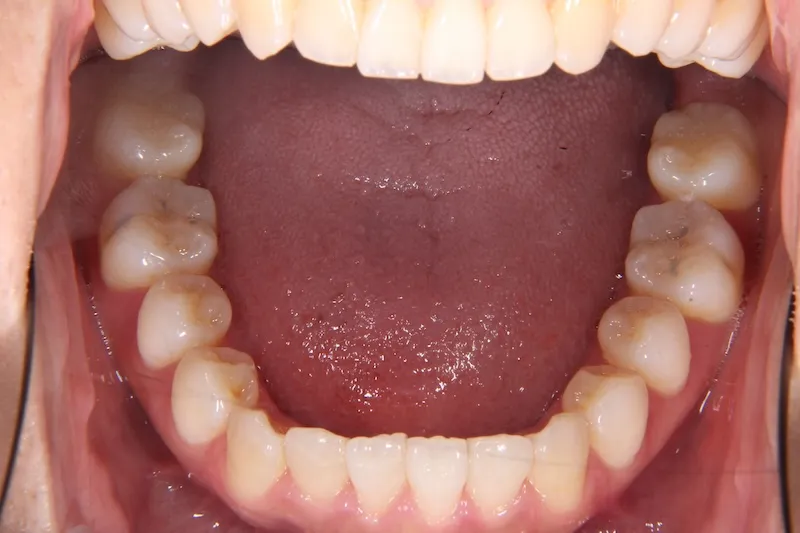

治療経過1

前歯で物が噛みちぎれないを主訴に来院された患者様です。

非抜歯で、オリジナルリンガルアーチと歯科矯正用アンカースクリューを用いて治療しました。

治療回数15回、1年の治療期間で矯正治療を終了しました。

主訴が改善され、ご満足頂きました。